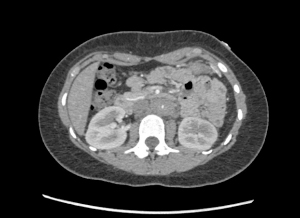

Patient underwent CT angiogram of her chest and abdomen emergently and the findings were suspicious for “periaortitis in association with midaortic syndrome with severe stenosis/near occlusion of the infrarenal aorta, bilateral renal arteries, celiac trunk, and SMA.” Findings that could represent a vasculitis versus neoplastic process.

Occluded aorta